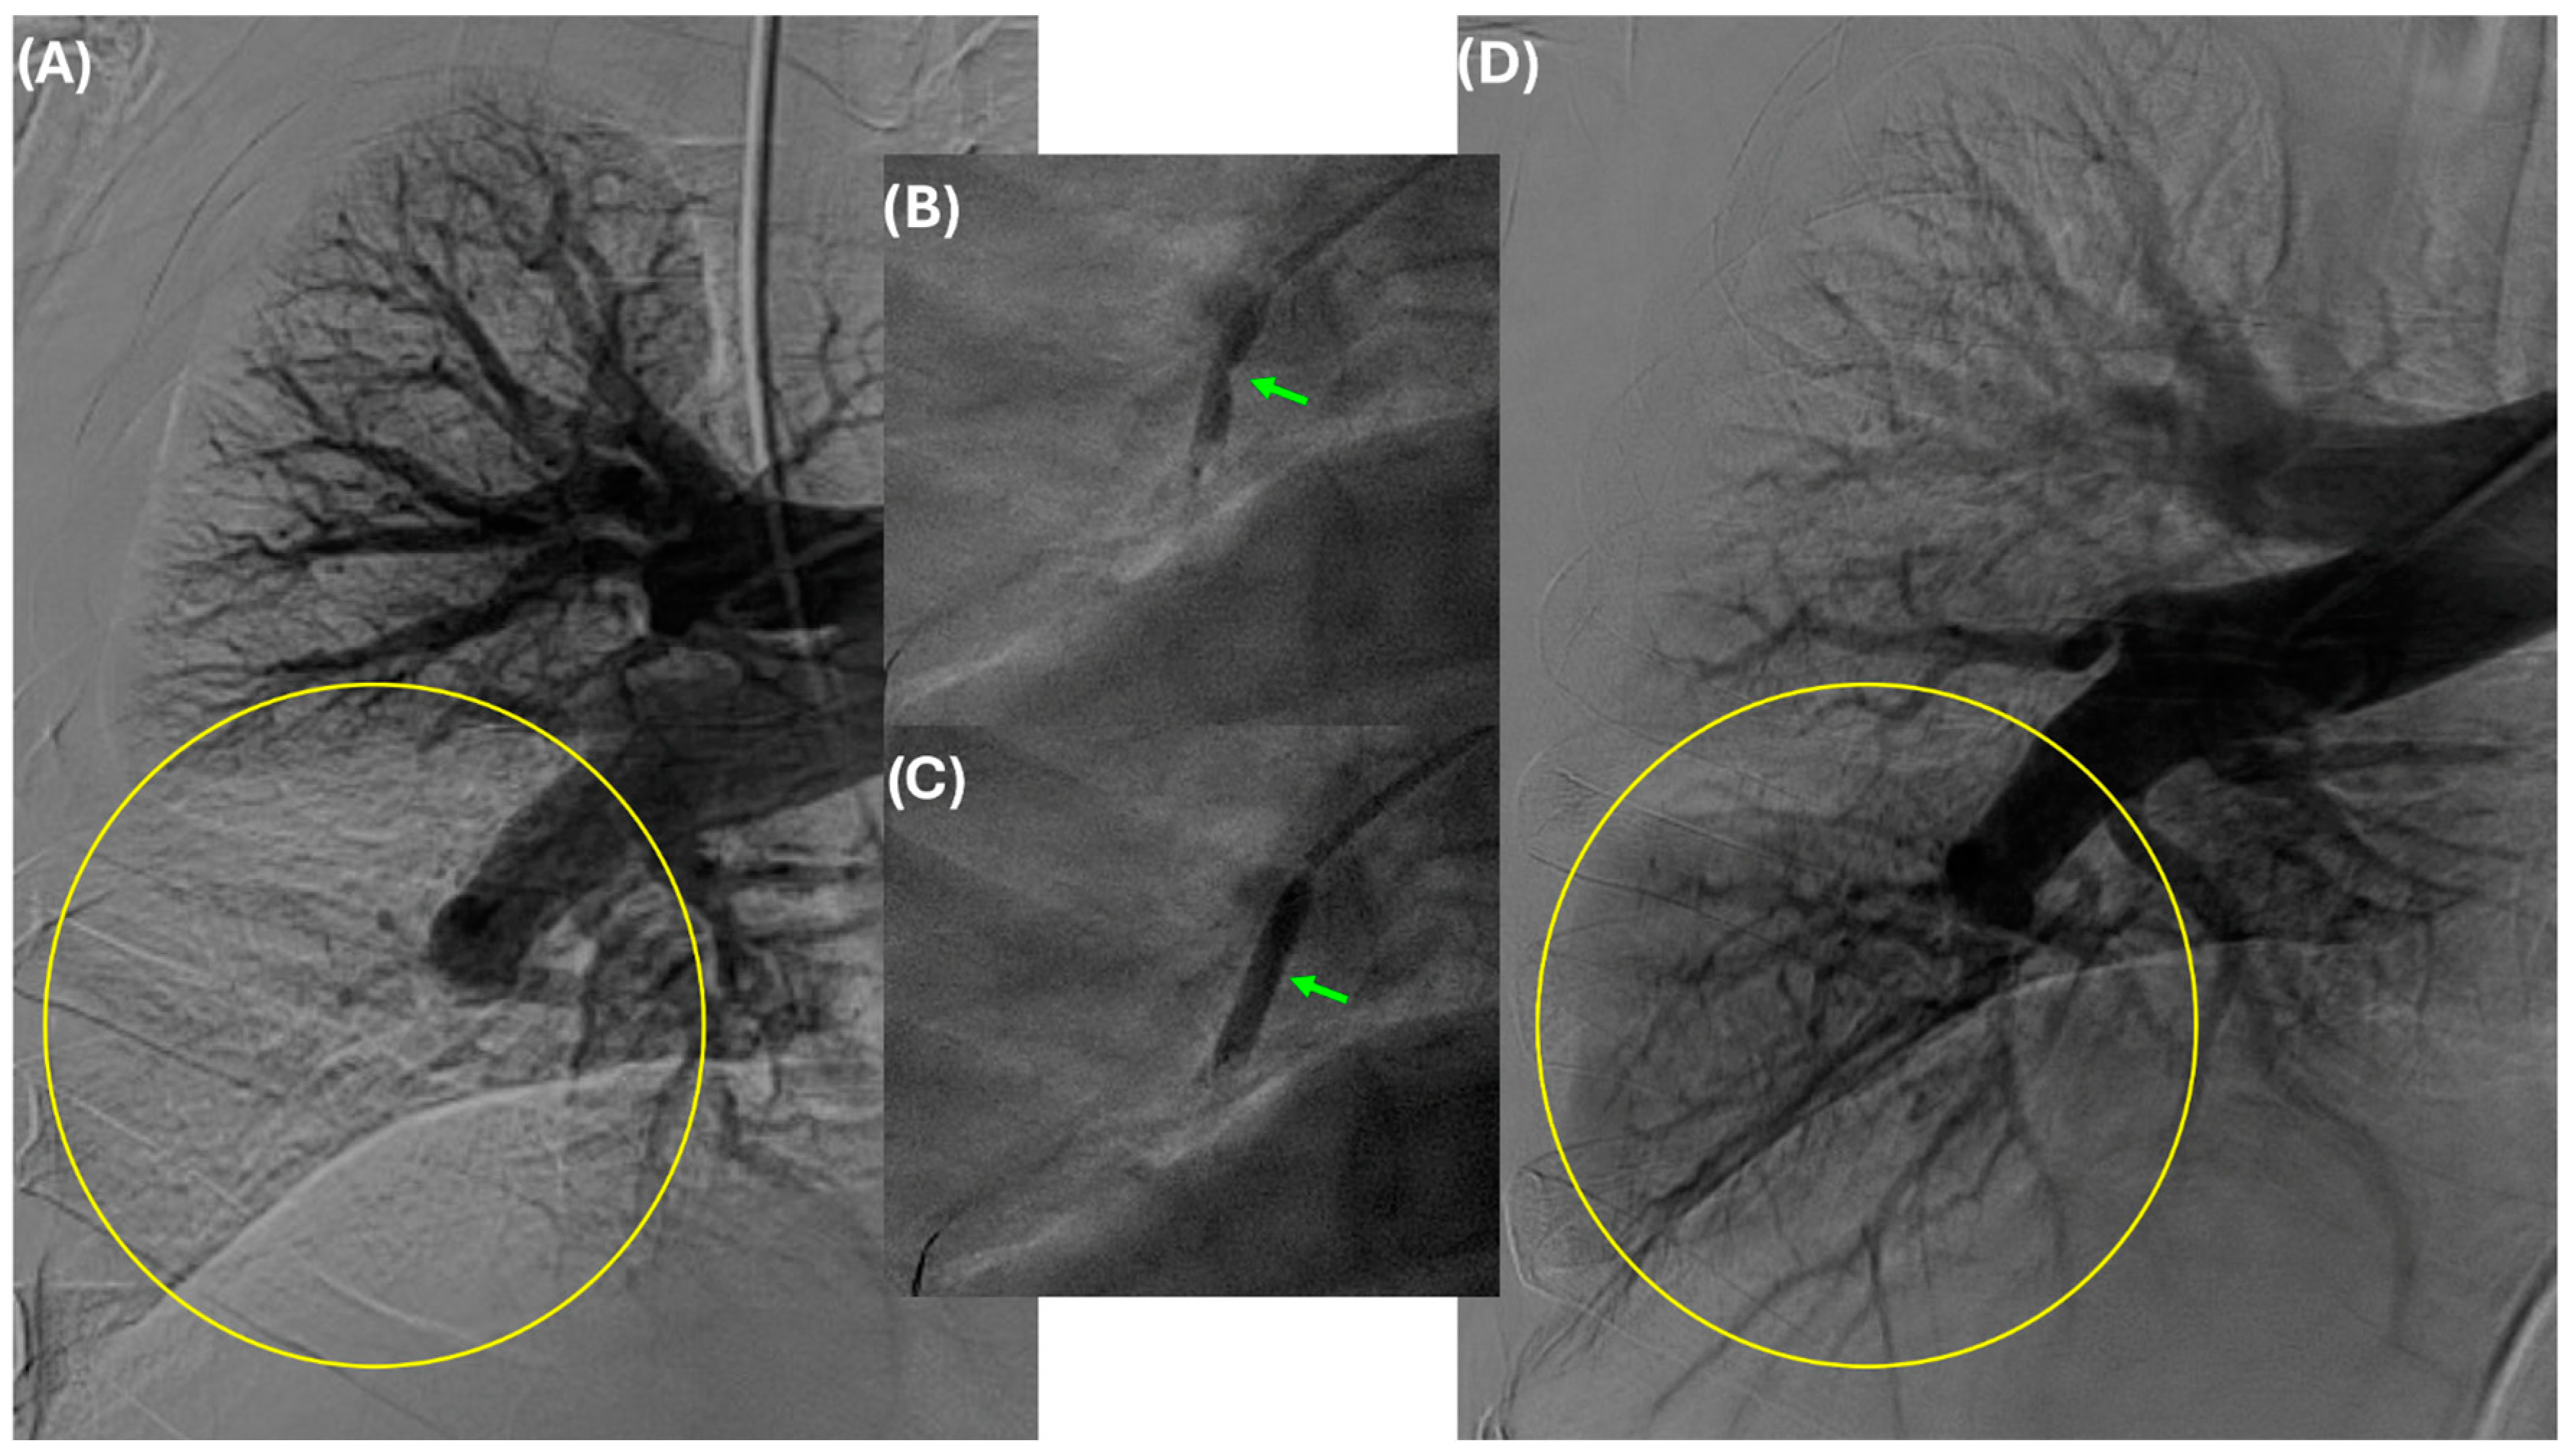

4. Indications and Patient Selection for BPA

5. Technical Considerations